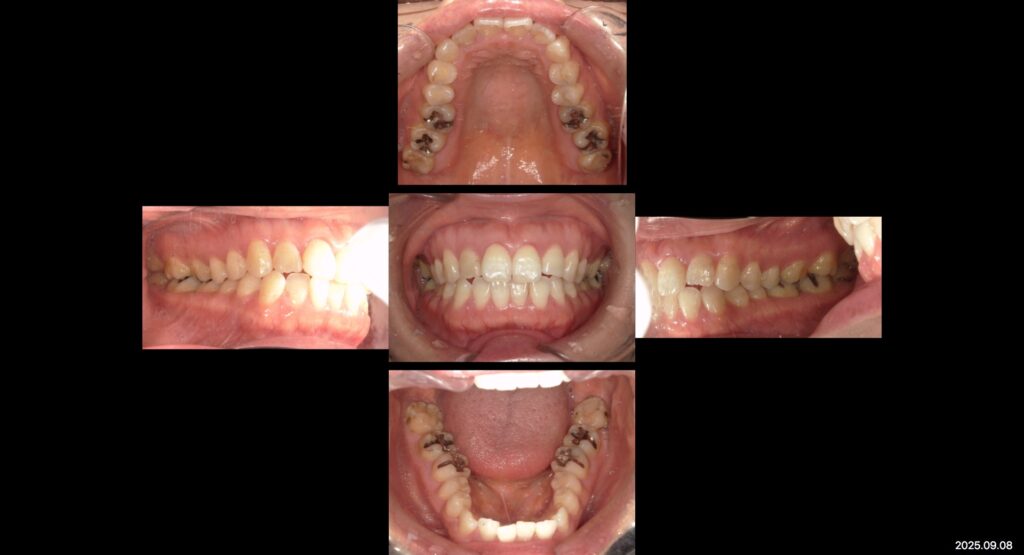

上:初診時口腔内写真

主訴

銀歯を白くしたい

治療内容

左上6,7 右上6,7 左下6,7 右下6,7

In→e-max In

右上2 左下1

Cr→e-max cr(ナチュラルカラー)

年齢

44歳

性別

女性

目的

見た目・噛み合わせの改善

副作用

一時的しみる

治療期間

約6ヶ月

費用

約76万円

来院回数

20回

本日は補綴治療を終えた患者様の症例写真です✨

見た目と噛み合わせ改善を目的に銀をセラミックの補綴物に替える根本治療を行いました。